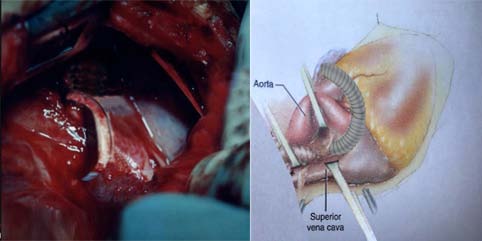

Therefore the decision was made to a new palliative surgical procedure for the first time. In order to preoperative medical stabilizing we administere 100% O 2 with the aim of promoting respiratory alkalosis as well as nitric oxide as a pulmonary vascular dilator, since the patient had severe metabolic acidosis besides Pulmonary hypertension (PHT). Under general anesthesia, median sternotomy and partial thymectomy were carried out. The pericardium was opened in vertical fashion then prudent purse-string sutures as standby were placed on ascending aorta and right atrial appendage (without using CPB). After intravenous heparinization (100 U/kg), at first some dissections were done from left lateral side between heart and pulmonary venous confluence then the dome of the left atrium was exposed. The posterior pericardium just superior the dome of LA was incised and PVC was appeared (fig. 2). Using a side -biting clamp on the PVC, a longitudinal incision was made. The proximal head of a Gore-Tex (ePTFE) with appropriate size (diameter= 6 mm) that had been prepared and beveled, was anastomosed to PVC using continuous 6-0 polypropylene suture. Under topical cooling of heart and using a side-biting clamp on left atrial appendage (LAA), the distal end of Gore-Tex was anastomosed to LAA. After deairing with heparinized saline as routine, the clamp was removed. The Sarmast-Takriti Shunt (STS) between PVC and LA was established (fig. 3). Immediately after completion of the procedure, cyanosis began to decrease. We performed the main operation 7-months later with excellent outcome when he had already sustained satisfactory weight (w= 7030 gr), as follows: After the establishment of CPB, the shunt was removed. To reduce the risk of residual obstruction of PVC due to pocket-like contraction our team preferred modified septosuperior approach (komarakshi technique). A direct anastomosis between PVC and L. A, ligation of the VV and closure of ASD with autopericardial patch were achieved in one stage repair.